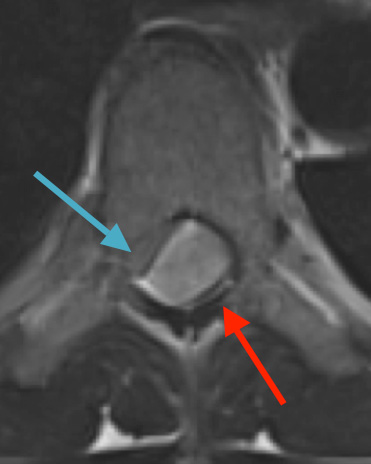

Postoperative MRI T2 illustrating the restoration of CSF surrounding the cord (blue arrow)

Pathology came back as Atypical Meningioma, WHO grade 2. Postoperative MRI showed a gross total resection without residual tumor, and appropriate spinal cord re-expansion. On her most recent follow-up at 6 weeks, she was very pleased with the results from the surgery. She reports resolution of her preoperative thoracic back and radicular pain, and great improvement with her ability to ambulate and overall function. It is demonstrated by her interval VAS of 2/10, and ODI of 23/100. She is expected to continue improving with time and therapy. Follow-up plan is to observe with radiographic surveillance.